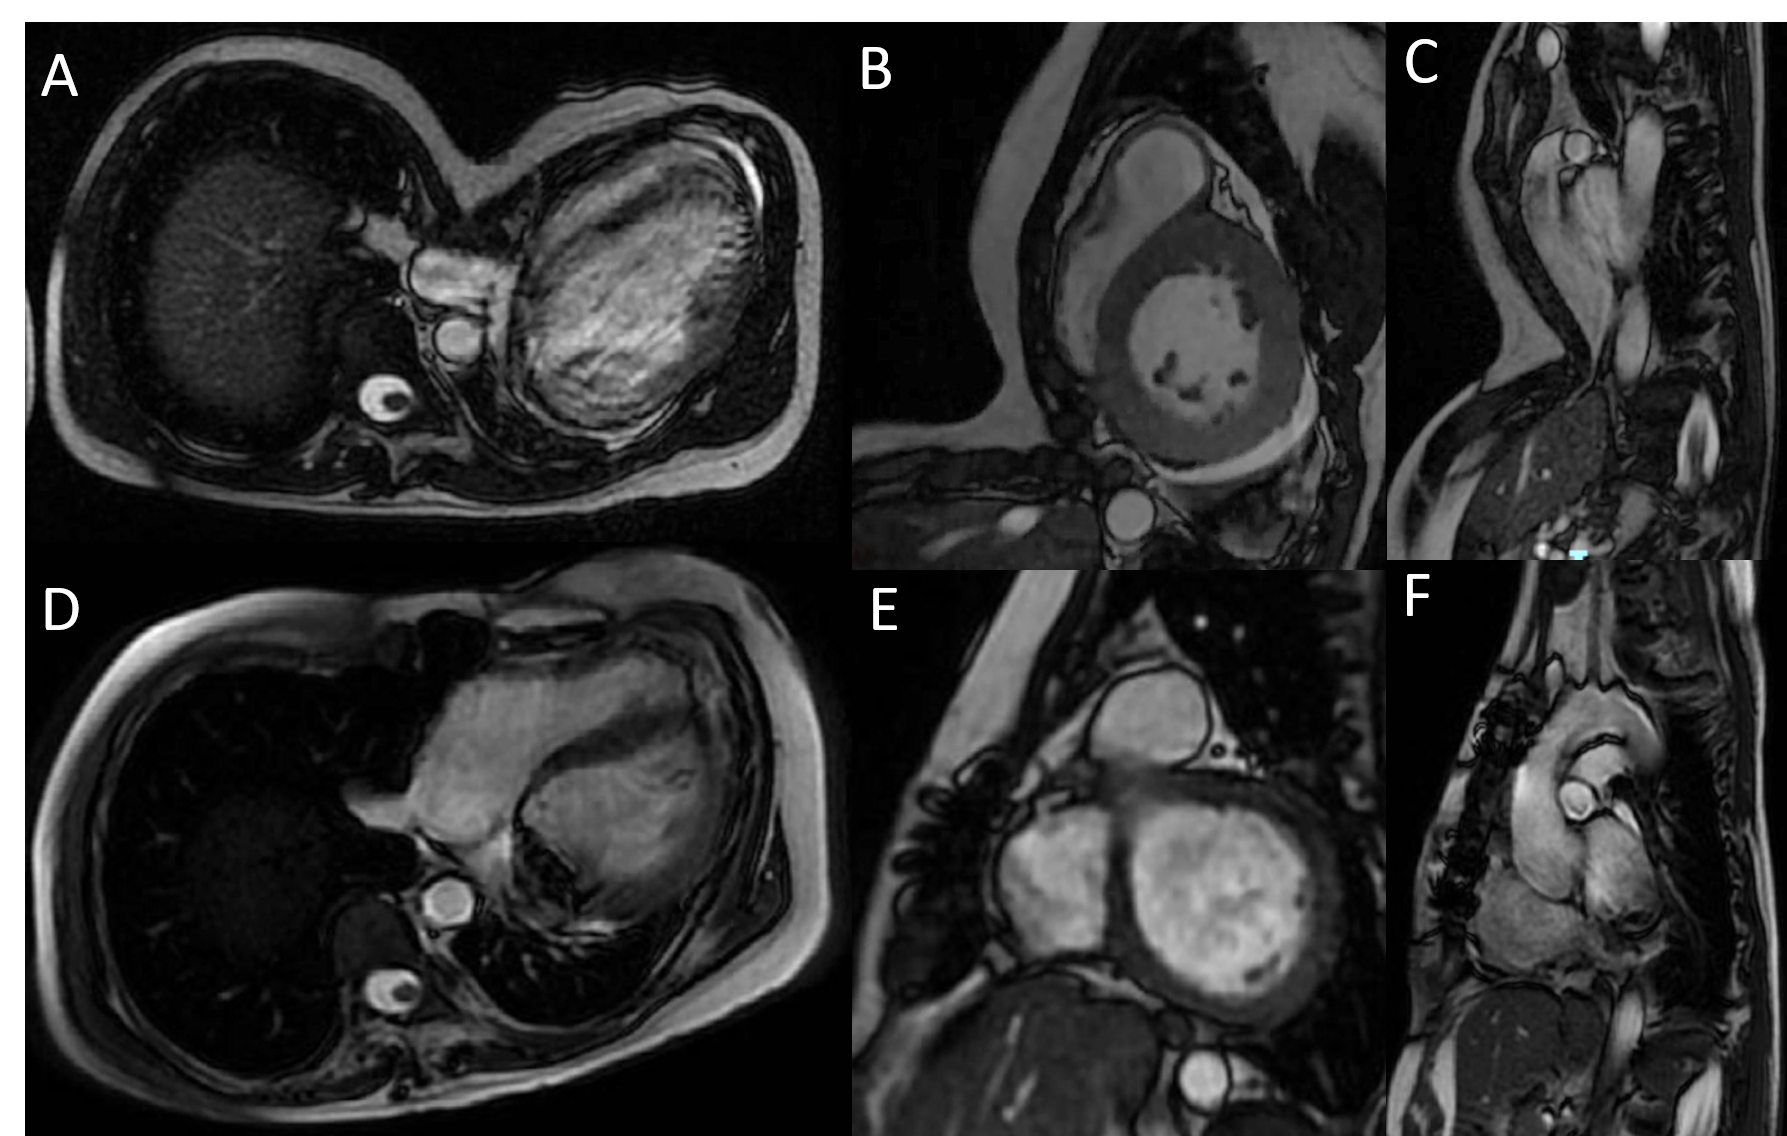

Fig. 2: A-B-C.- Presurgical CMR. D-E-F.- Postsurgical CMR